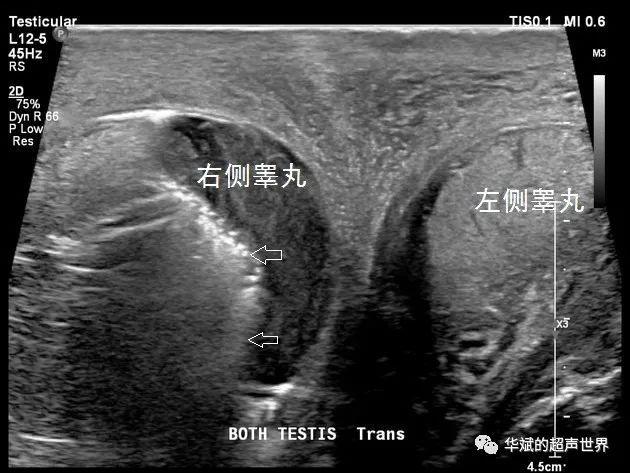

典型病例61福涅尔坏疽与气肿性睾丸附睾炎的鉴别坏死性筋膜炎气肿性